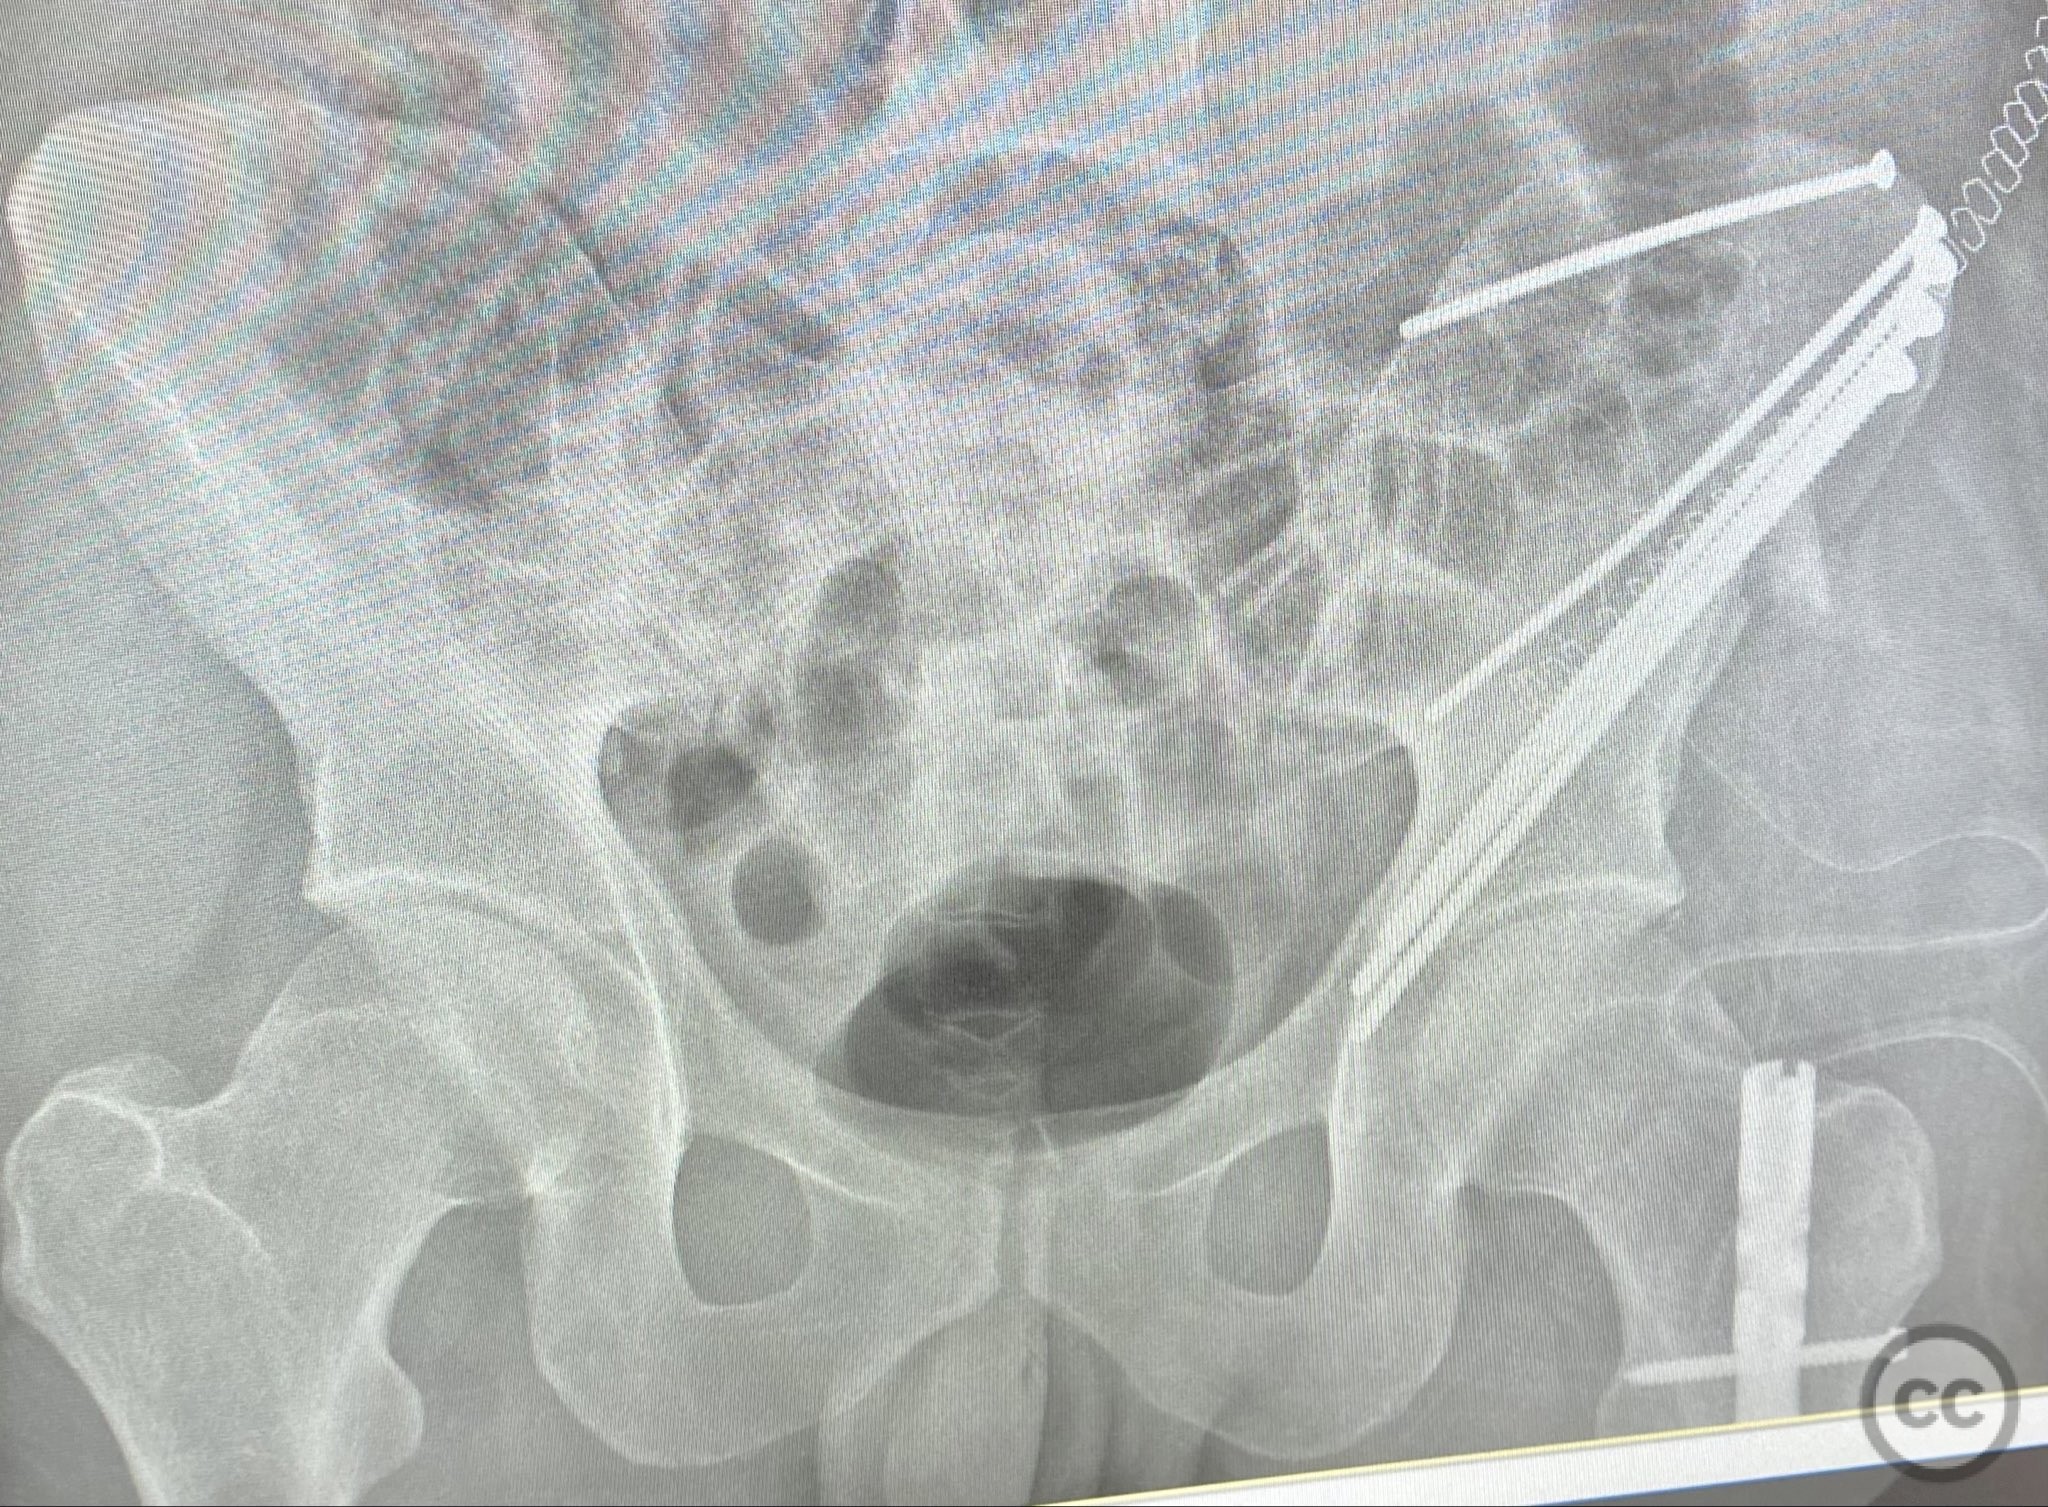

Clinical and radiological findings:  A patient sustained a high-energy injury resulting in an open, comminuted fracture of the iliac wing, sparing the pelvic ring. Associated injuries included spine, rib, and femur fractures. Initial radiographs and axial CT imaging demonstrated significant comminution of the iliac wing with intraosseous air densities indicative of an open wound. No pelvic ring disruption was identified. AO/OTA classification: 61-A2. The presence of multiple associated injuries is consistent with a direct lateral load mechanism.

Planning remarks:  The preoperative plan included emergent irrigation and debridement of the traumatic open wound, followed by anatomical exposure of the iliac wing for further irrigation and debridement. Fracture stabilization was planned using lag screw fixation between the iliac cortices to minimize implant prominence and reduce infection risk.

Orthopaedic implants used:   4.5mm cortical lag screws, 3.5mm cortical lag screws